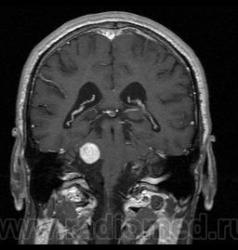

Пациент 35 лет, направлен неврологом из поликлиники с Ds: Рассеянный склероз? У данного пациента в течении года отмечается сильное головокружение и шаткость в походке, пришел на исследование на плечах у родственников. Данное исследование закачено на Dicom-сервер http: //www.radiomed.ru:8080/oviyam/oviyam? (под названием Brain-20101118).

Невринома правого слухового нерва

Если быть точным, VIII нерва;)

Более вероятнее невринома правого слухового нерва.